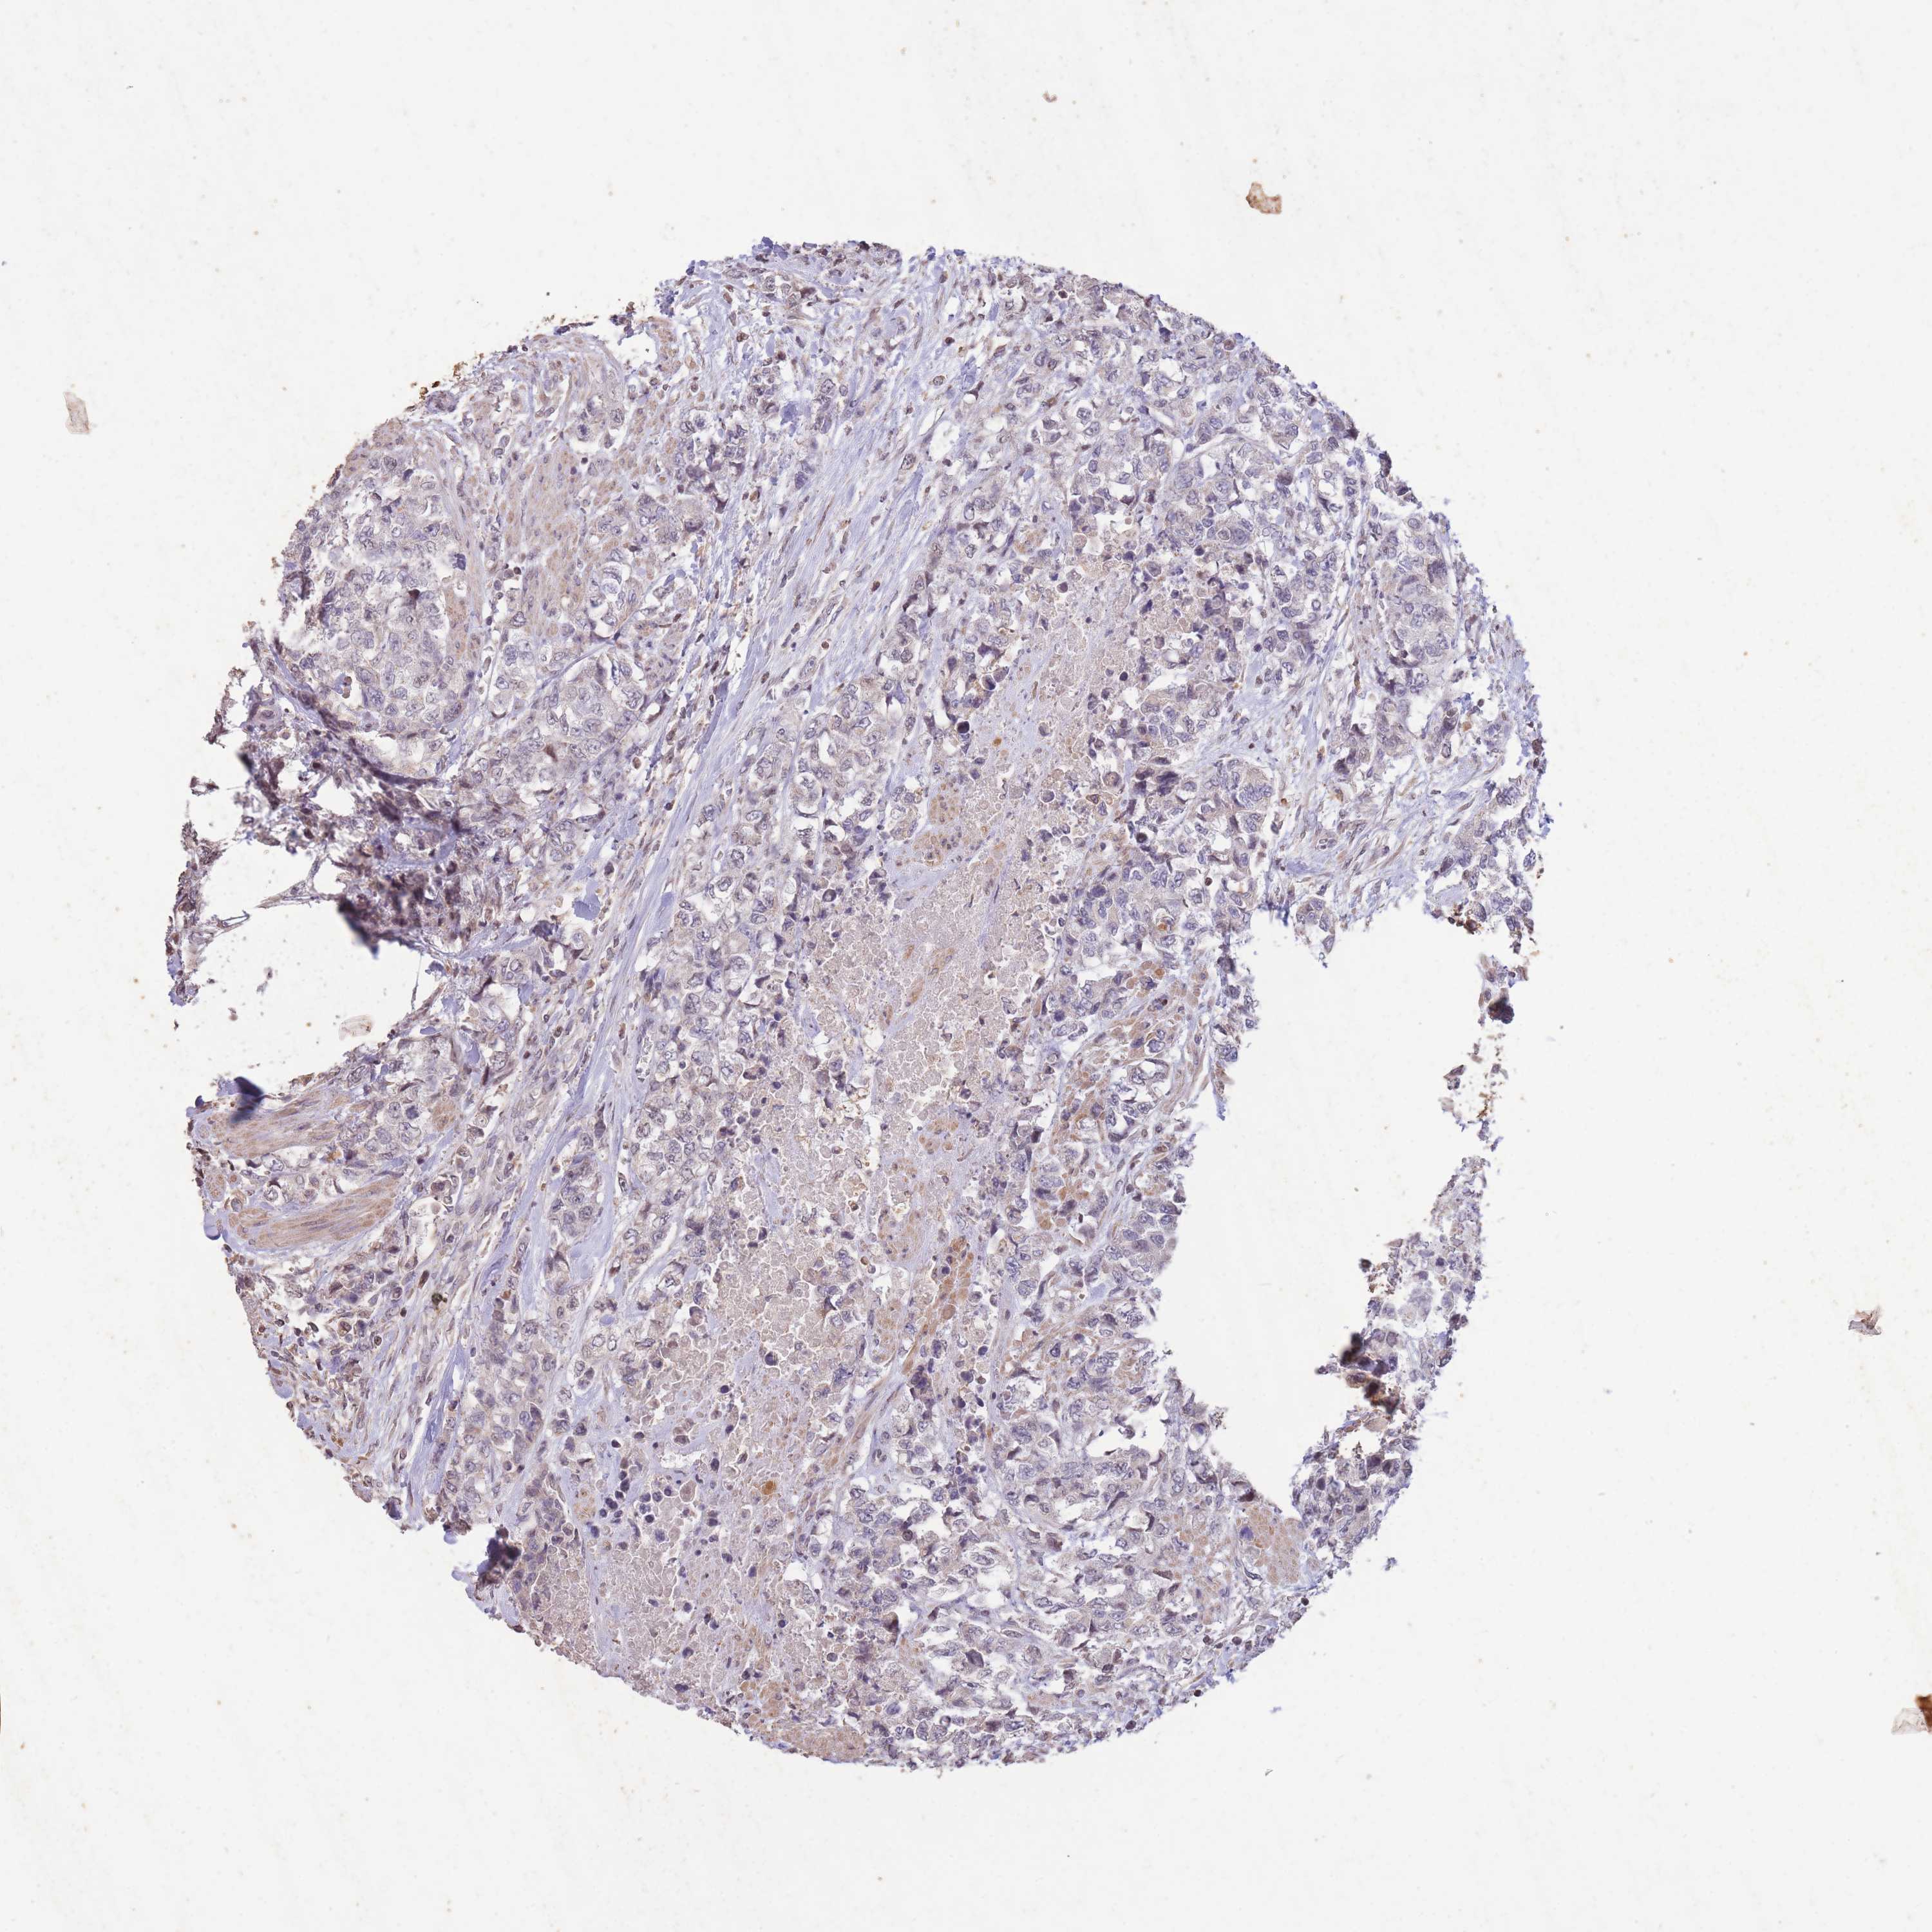

UROTHELIAL CANCER - Protein expressioni

A mouse-over function shows sample information and annotation data. Click on an image to view it in a full screen mode. Samples can be filtered based on level of antibody staining by selecting one or several of the following categories: high, medium, low and not detected. The assay and annotation is described here.

Note that samples used for immunohistochemistry by the Human Protein Atlas do not correspond to samples in the TCGA dataset.

Antibody stainingi

Antibody staining in the annotated cell types in the current human tissue is reported as not detected, low, medium, or high, based on conventional immunohistochemistry profiling in selected tissues. This score is based on the combination of the staining intensity and fraction of stained cells.

Each image is clickable and will lead to virtual microscopy that enables deeper exploration of all samples and also displays staining intensity scores, fraction scores and subcellular localization as well as patient and tissue information for each sample.

Antibody HPA046847

Staining

High

Medium

Low

Not detected

Intensity

Strong

Moderate

Weak

Negative

Quantity

>75%

75%-25%

<25%

None

Location

Nuclear

Cytoplasmic/membranous

Cytoplasmic/membranous,nuclear

Urothelial carcinoma, Low grade

Urothelial carcinoma, High grade

Urothelial carcinoma, NOS